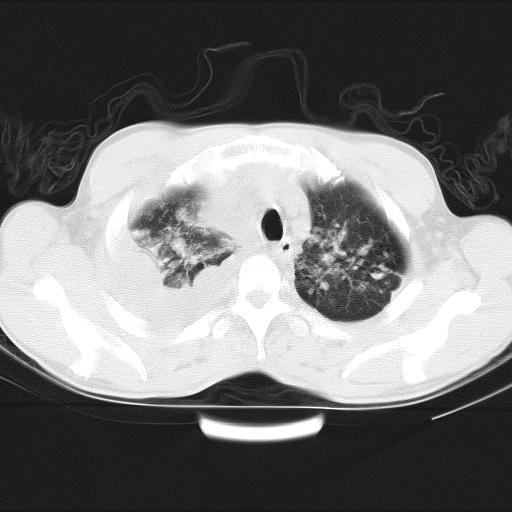

男性,44岁,结核病史多年。现胸闷气短,咳嗽,偶咳血。

双肺多发结节影最分空洞形成考虑占位不除外结核

1)两肺继发性肺结核伴空洞形成,左肺多发性结核球。2)右侧大量胸腔积液伴右肺部分膨胀不全。3)纵隔淋巴结肿大。

1,双肺多发结节 并空洞影改变, 左侧胸腔积液并部分包裹, 结合原病史首先考虑结核. 但也不除外其它.

2,左侧有一根肋骨陈旧性骨折? 建议追查 .

吉大一院胸水抽检结果:结核性胸水